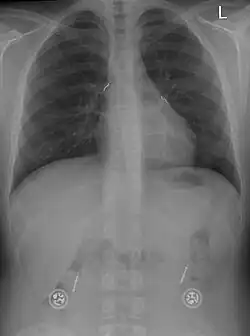

Etwa 17 % der Undine-Kinder atmen auch während des Wachzustandes nicht ausreichend, sodass sie 24 Stunden am Tag beatmet werden müssen. Viele dieser Kinder sind mit einem Zwerchfellschrittmacher versorgt und dadurch mobil. Atmen Undine-Patienten tagsüber spontan, so bietet sich eine nächtliche Beatmung mit Nasenmaske an. Einige Kinder werden nach Geburt zunächst mit einem Tracheostoma beatmet und im Kindergarten- oder Grundschulalter auf Maske umgestellt.